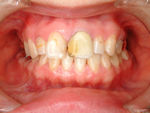

◆オールセラミック修復

~修復前~

オールセラミック修復

~修復後~

~修復後拡大~